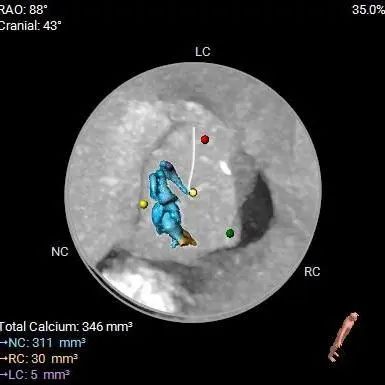

钙化分析:

HU850

钙化分布

三叶式主动脉瓣,瓣叶轻中度钙化并明显增厚,人工瓣膜锚定力尚可,左室流出道呈敞口型,综合多平面分析,预估瓣膜释放后有向下位移风险及瓣周漏可能。